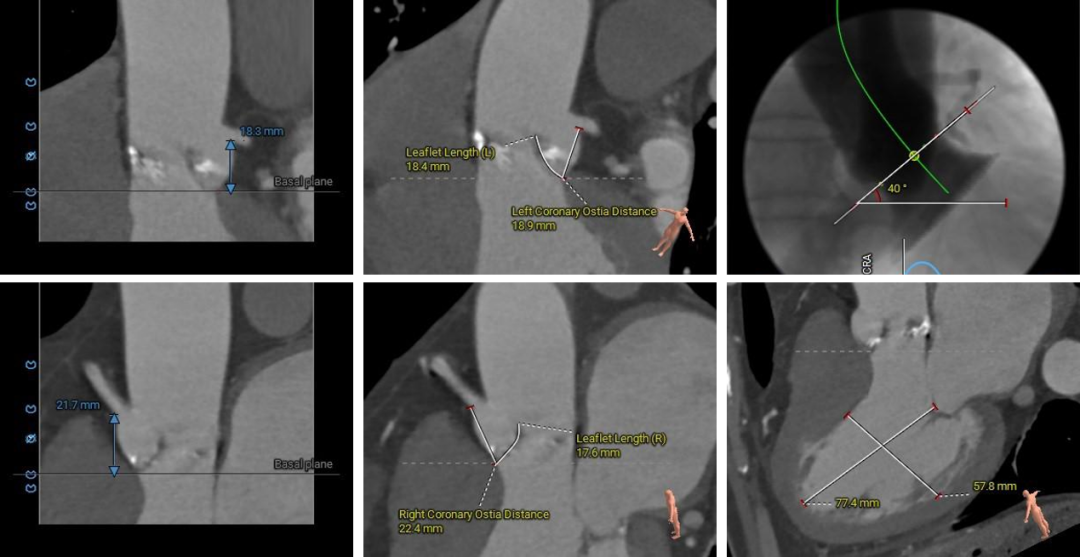

冠脉阻挡风险、左室大小及横位心评估

5.主动脉瓣环与水平面夹角为40° ,主动脉弓部夹角及弓距尚可;

2.冠脉开口高度尚可,切线位未见左右冠瓣叶冗长;

1.Type1型二叶式主动脉瓣,瓣叶增厚伴中度钙化,左右窦间可见钙化融合嵴,钙化主要分布于无冠窦瓣叶边缘以及左右瓣叶交合缘,左室流出道为类直筒型;

3.瓦氏窦、窦管交界、升主动脉内径尚可;

4.左室腔内径明显偏大,心室壁厚度尚可;